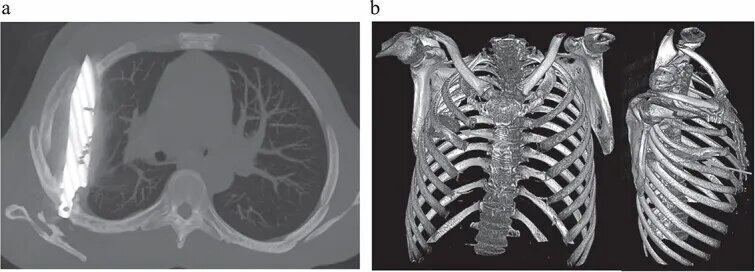

نوشته و ویرایش شده توسط مجله ی دانستنی کد خبر: ۲۸۶۶۹۷ تاریخ انتشار کردن: پنجشنبه ۰۳ مهر ۱۴۰۴ – ۱۴:۰۹ به نقل از بهداشت نیوز، در یکی از نادرترین موارد پزشکی ثبت‌شده، مردی ۴۴ ساله اهل تانزانیا با ترشح چرک از قفسه سینه‌اش به اورژانس مراجعه کرد؛ اما آنچه پزشکان کشف کردند، فراتر از انتظار می بود: تیغه‌ای فلزی از چاقو که سال‌ها پیش در جریان یک درگیری خشونت‌آمیز داخل بدنش شده و بی‌هیچ علامتی در حفره قفسه سینه‌اش باقی مانده می بود. این مرد به زمان ۱۰ روز ناظر خروج…